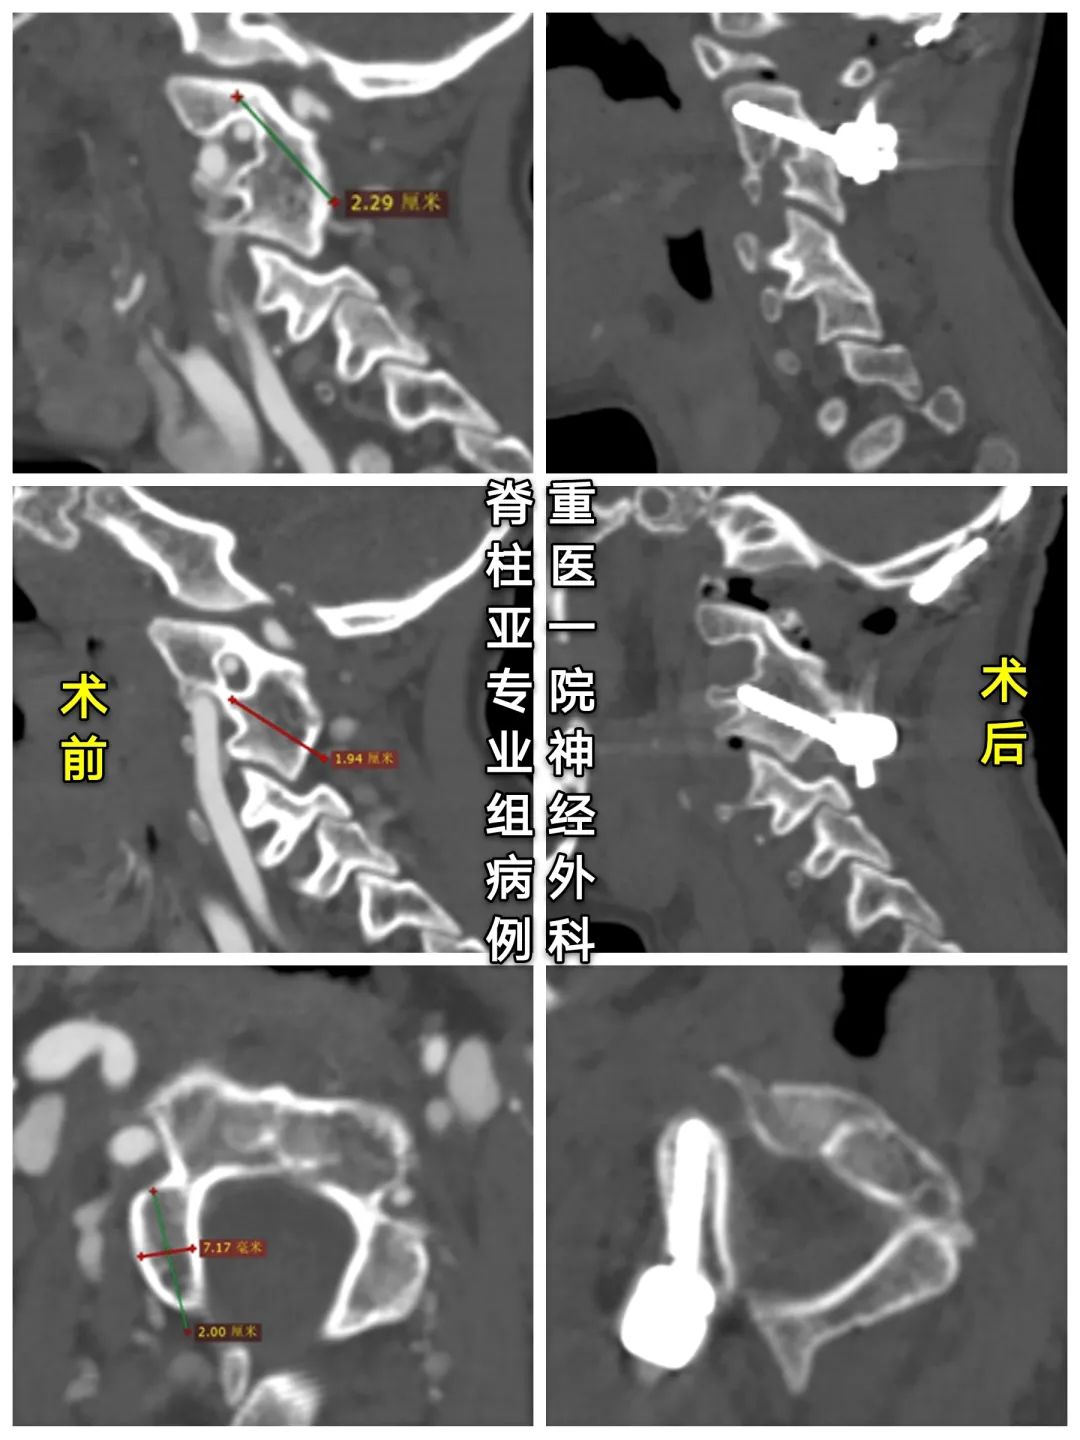

◆术前颈椎CT

寰椎右份缺如,与颈2、3椎体融合,颈4-6椎融合。

1、本例患儿斜颈,是由于C1发育不全、右侧侧块及后弓缺如所致。

3、术中恢复缺如的右侧C1侧块高度,并在在关节间植骨,以纠正斜颈。